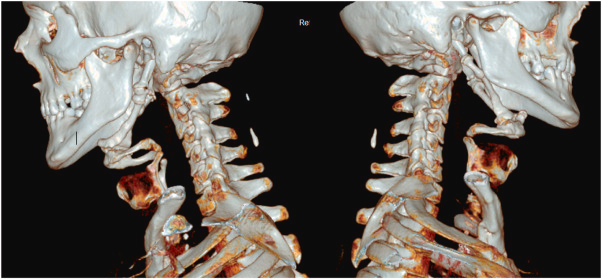

The correct answer for the poll below was actually "Eagle's Syndrome related trauma"! The patient had bilaterally elongated styloid processes seen in the image below, which along with calcified stylohyoid ligaments and the hyoid formed a ring in the neck sciencedirect.com/science/articl…

The ossification of these ligaments meant the loss of flexibility and, rather than accommodate the applied force, maintained their structure and pierced the retro-pharynx! Link to the case report is above!